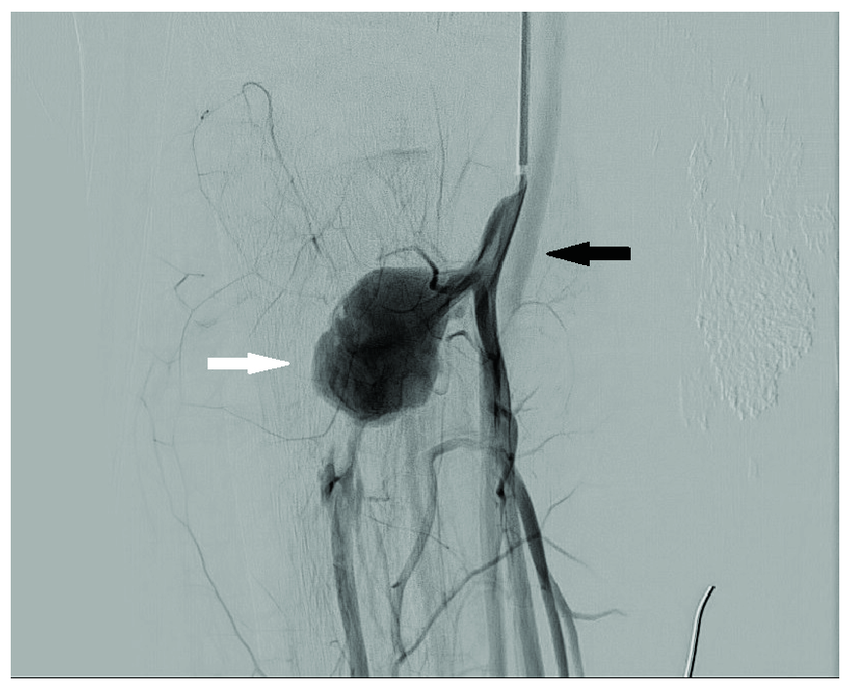

硬脊膜動(dòng)靜脈瘺逐步排查瘺口,精準(zhǔn)治療硬脊膜動(dòng)靜脈瘺診斷的金標(biāo)準(zhǔn)是選擇性血管造影(DSA),不僅可以定性診斷,還可以明確瘺口的位置。主要治療方式有手術(shù)夾閉瘺口和血管內(nèi)栓塞,手術(shù)方式治療的核心在于半椎板開椎夾閉或切斷瘺口

治療前患者2年前即出血下肢乏力,但是行動(dòng)基本正常,當(dāng)時(shí)脊髓核磁共振檢查硬脊膜下脊髓表面滿布擴(kuò)張迂曲血管,建議行脊髓血管造影檢查,但是患者懼怕手術(shù),2年來下肢乏力進(jìn)行性加重,無法行走了才決定住院手術(shù)治療。入院時(shí)由輪椅推行入院。治療后治療后7天原本以為手術(shù)后短期內(nèi)可能看不到明顯效果,結(jié)果術(shù)后3天患者雙下肢即可不太費(fèi)力抬離床面,比術(shù)前有改善,術(shù)后1周患者雙下肢肌力進(jìn)一步好轉(zhuǎn),可以杵拐杖下地行走,患者本人很高興,作為手術(shù)醫(yī)生也感到一些欣慰。治療后即刻入院后第一次脊髓血管造影沒有找到畸形血管漏口,因臨床表現(xiàn)及全脊髓核磁共振檢查均為典型表現(xiàn),反復(fù)與患者家屬溝通商議,告訴患者家屬肯定存在畸形血管,只是沒有找到漏口,是否愿意休息數(shù)日后再次行全脊髓血管造影(因脊髓供血血管很多,脊髓血管造影相對(duì)全腦血管造影復(fù)雜很多,工作量多很多倍,對(duì)于醫(yī)生和患者都是很大的考驗(yàn)),家屬商議后果斷決定再次造影檢查,手術(shù)排在雜交(復(fù)合)手術(shù)間,以便第二次造影一旦發(fā)現(xiàn)漏口即翻身開刀處理供血?jiǎng)用}及漏口,全脊髓血管造影在脊髓血管造影經(jīng)驗(yàn)最豐富的向守衛(wèi)醫(yī)生的努力堅(jiān)持下,從頸部一直到骶尾部,在身體的最低位置發(fā)現(xiàn)了漏口(就像密碼箱忘記密碼了,一個(gè)數(shù)字一個(gè)數(shù)字的嘗試,直到嘗試到最后一個(gè)數(shù)字才試出來?。?,找到漏口后切開骶尾部皮膚及骶尾部椎管,看到造影定位處硬脊膜表面血供豐富,切開硬膜即可見極為粗大的引流血管,給予動(dòng)脈瘤夾夾閉引流血管根部,再次術(shù)中造影證實(shí)此處即為漏口,隨即切斷漏口并關(guān)閉縫合切口,整個(gè)手術(shù)由下午持續(xù)到半夜才結(jié)束。